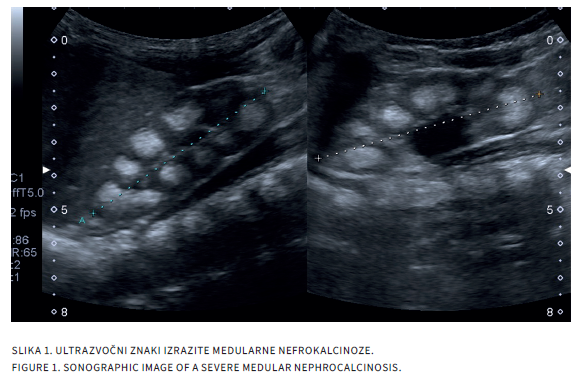

FAMILIAR HYPOMAGNESEMIA WITH HYPERCALCIURIJA AND NEPHROCALCINOSIS

Familial hypomagnesemia with hypercalciuria and nephrocalcinosis (FHHNC) is a rare autosomal recessive disorder. It is characterized by renal wasting of magnesium and calcium, associated with the development of nephrocalcnosis and renal stones in early childhood. FHHNC is a rare cause of nephrocalcinosis and/or kidney stones and should be considered when encountered in small child since it progressively and irreversibly leads to chronic kidney disease and end stage kidney failure no later then in the second or third decade of life. With agressive therapy which is exclusively symptomatic and includes fluid, dietary restrictions, potassium citrate and magnesium supplemention, progression to an end stage kindney disease could be postoponed.